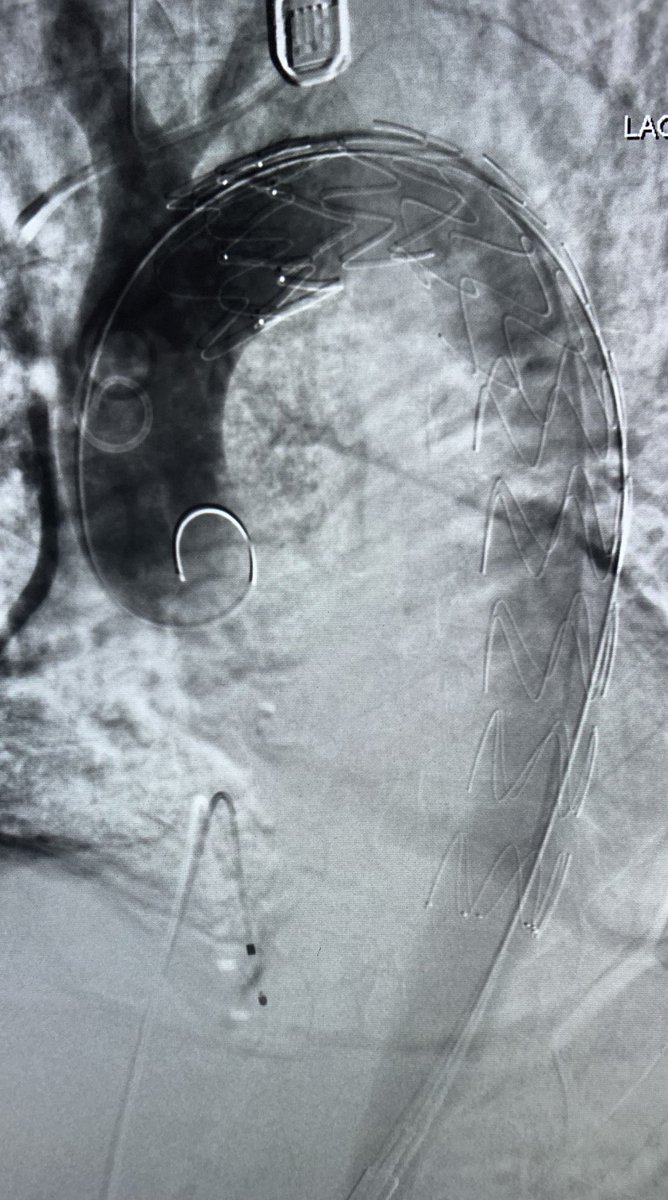

Type 1A endoleak with a short ascending graft and expanding arch. Our team’s first experience using the Bolton Arch graft. Really precise deployment and easy cannulation of the tunnels @TerumoAortic @CAIRweb #aorta